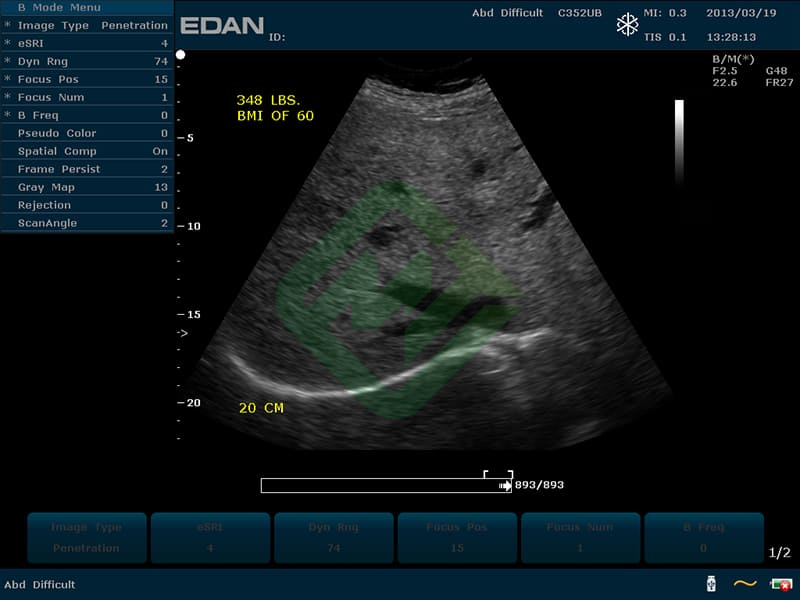

— конвексным C352UB: частотный диапазон датчика 2–6 МГц, угол обзора 70°, глубина сканирования 320 мм, количество элементов 128